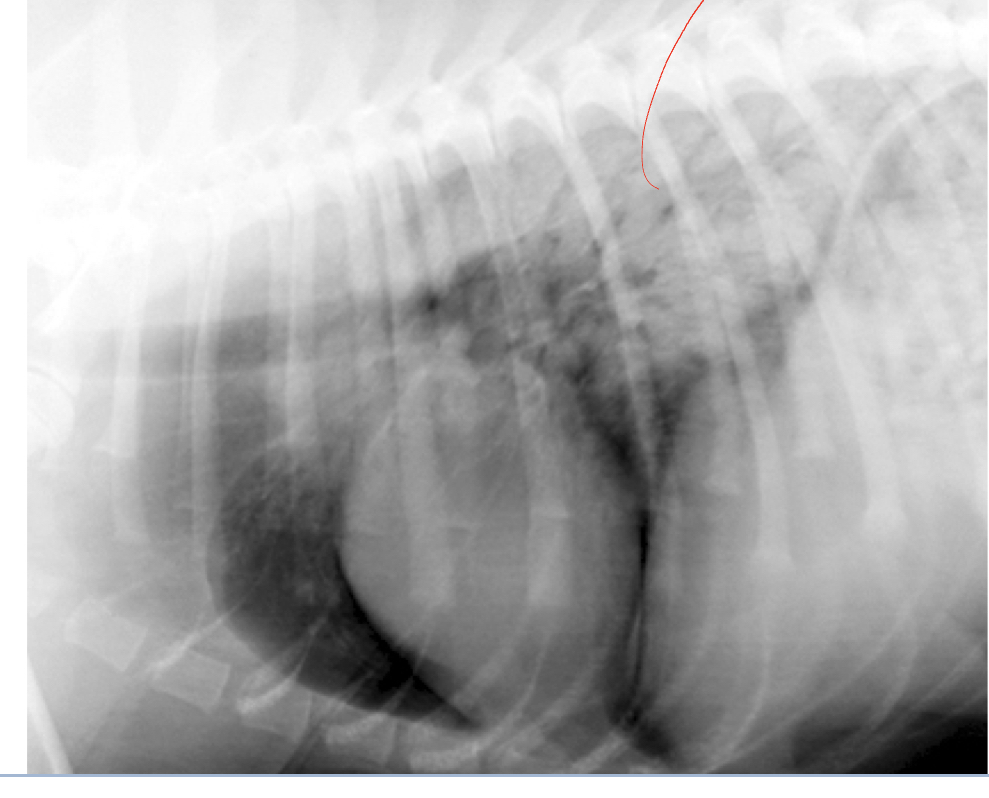

Q

classify the location/pattern and what is likely ddx

A

caudodorsal

Ddx: cardiogenic or non-cardiogenic pulmonary edema

Likely non-cardiogenic pulmonary edema because cardiac silhouette looks fine